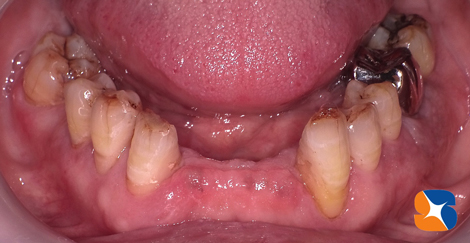

70代の紹介女性。主訴は「前歯がグラグラ。上の奥歯がない。噛む所がない。顔もくしゃってる」でした。

当院の入れ歯は、軽く、薄く、小さく、デザインにもこだわった渾身の入れ歯を保険料金で提供しています。最終、この様な入れ歯を装着することを目標に治療を始めた。 続きを読む